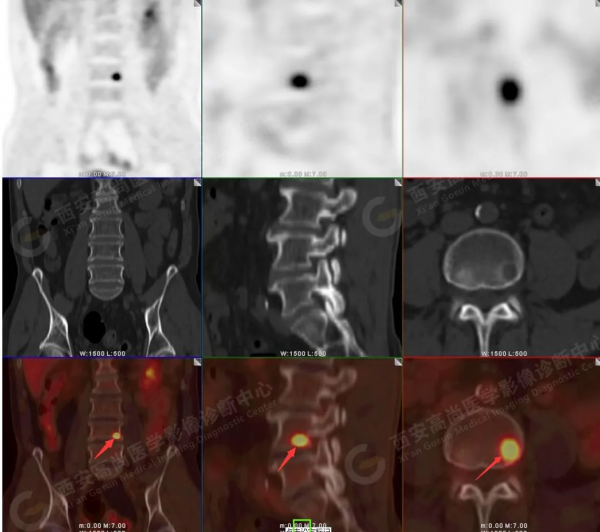

2.以下為部分全身多發轉移灶

5.右側肱骨上段、左側肩胛骨、右側鎖骨胸骨端、胸骨、雙側多發肋骨、脊柱多發椎體及附件、雙側髂骨、雙側髖臼、雙側恥骨、雙側肱骨上段多發成骨性病變,呈不同程度FDG代謝異常增高,考慮為多發骨轉移瘤。

以上病變符合:T4N3M1c,ⅣB期(UICC/AJCC,2018年第8版肺癌TNM分期)。